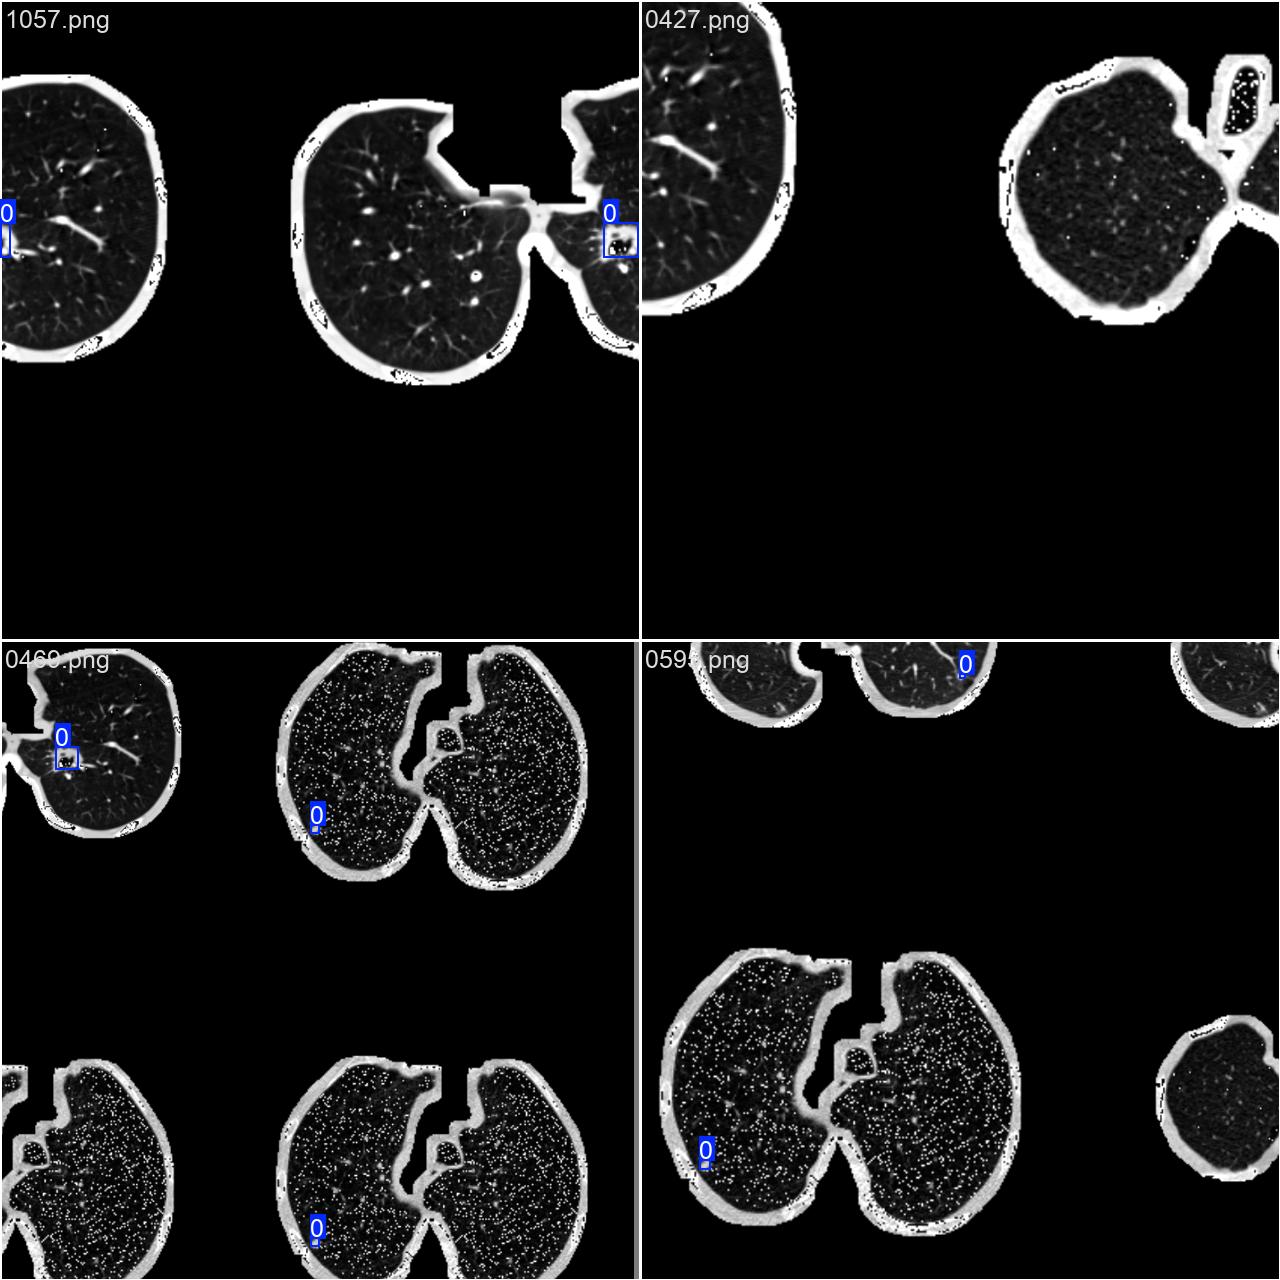

2.数据集准备与训练

本研究使用了包含各种肺结节相关图像的数据集,并通过Labelimg标注工具对每张图像中的目标边框(Bounding Box)及其类别进行标注。然后主要基于YOLOv8n这种模型进行模型的训练,训练完成后对模型在验证集上的表现进行全面的性能评估及对比分析。模型训练和评估流程基本一致,包括:数据集准备、模型训练、模型评估。本次标注的目标类别为肺结节,数据集中共计包含1186张图像,其中训练集占938张,验证集占248张。部分图像如下图所示:

部分标注如下图所示: